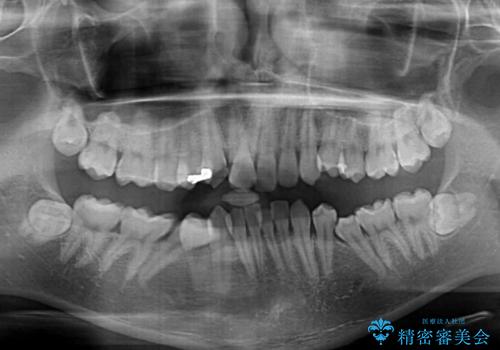

- 「前歯のデコボコが気になる」「前歯の中心がずれていて気になる」とご相談に来られた患者様の症例です。

診察の結果、上下の歯が並ぶためのスペースが不足しており、特に上顎右側の側切歯が内側(口蓋側)に転移していたため、正中が大きく右にずれている状態でした。

上下左右の第一小臼歯を抜歯してスペースを確保する計画を立てました。